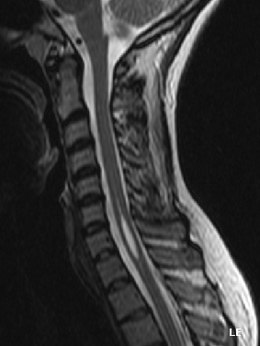

- Syrengomyélie IRM.jpg (15.2 Kio) Vu 241 fois

Tu peux voir ci-dessus, sur cet IRM du profil de la partie haute du rachis, la moelle spinale en gris au centre du canal médullaire du rachis. On voit une forme fuselée plus claire que la moelle et qui semble se trouver au centre de celle-ci, c'est la syringomyélie, càd qu'ici on a du LCR au milieu de la moelle qui s'écoule donc dans le canal central de la moelle. Cette zone a d'ailleurs le même signal (la même couleur) que le LCR qui entoure la moelle spinale.